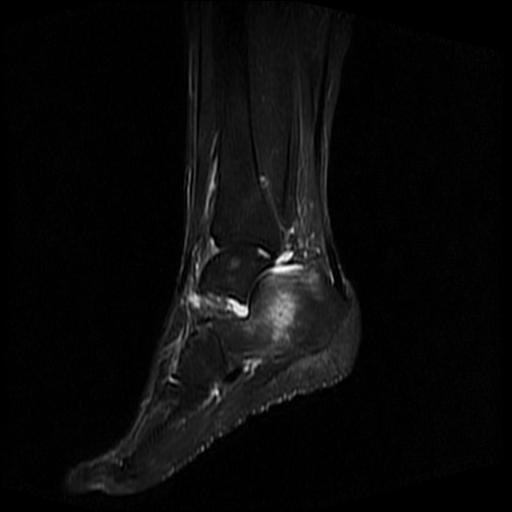

标题: MRI0968:女性,70岁,跟骨信号异常 [打印本页]

标题: MRI0968:女性,70岁,跟骨信号异常

女性,70岁,右侧跟骨疼痛2个月,负重时加剧,不负重时不疼。

跟骨长t1长t2信号异常,边缘模糊(肿瘤一般边界清楚,故肿瘤不考虑),压脂像呈高信号--骨髓水肿(炎症?)。